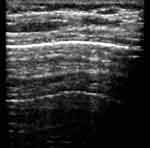

В норме при сканировании датчиком 7,5 МГц последовательно визуализировались следующие структуры: гипоэхогенный слой подкожной жировой клетчатки, тонкая эхогенная полоска наружного листка собственной фасции груди, гипоэхогенные мышечные слои, представленные мышцами плечевого пояса, брюшной стенки и межреберными мышцами с разделяющими их листками фасций. Мышечную ткань нетрудно отличить от жировой клетчатки, даже если полоска фасции отчетливо не видна. Глубже визуализируется эхогенная полоска внутренней грудной фасции, тонкий гипоэхогенный слой рыхлой клетчатки. Затем более тонкая эхогенная полоска, толщиной до 1 мм, являющаяся суммой отражения от париетального, висцерального листков плевры и границы мягкие ткани/воздушная легочная ткань. Просвет между листками плевры не виден. Наружный контур плевры ровный, можно увидеть зазубрину, соответствующую междолевой щели, а внутренняя поверхность эхогенной плевральной полоски не такая четкая и ровная, как наружная. Под ней регистрируются отдельные точечные эхосигналы. При дыхании отчетливо видно скольжение плевральных листков, вместе с висцеральным листком смещаются и точечные эхосигналы. Далее идут постепенно затухающие реверберации отражения от поверхности воздушной легочной ткани (Рис. 1).

Если используется датчик 3,5 МГц можно дифференцировать гипоэхогенную подкожную жировую клетчатку и мышечный слой, затем визуализируется эхогенная полоска плевральных листков и границы воздушной легочной ткани. Ее толщина несколько больше, чем при сканировании датчиком 7,5 МГц и составляет 1-1,5 мм, возможно из-за более глубокого проникновения ультразвуковой волны в воздушную легочную ткань. Во время исследования обращали внимание на положение и подвижность нижних краев легких, их симметричность.